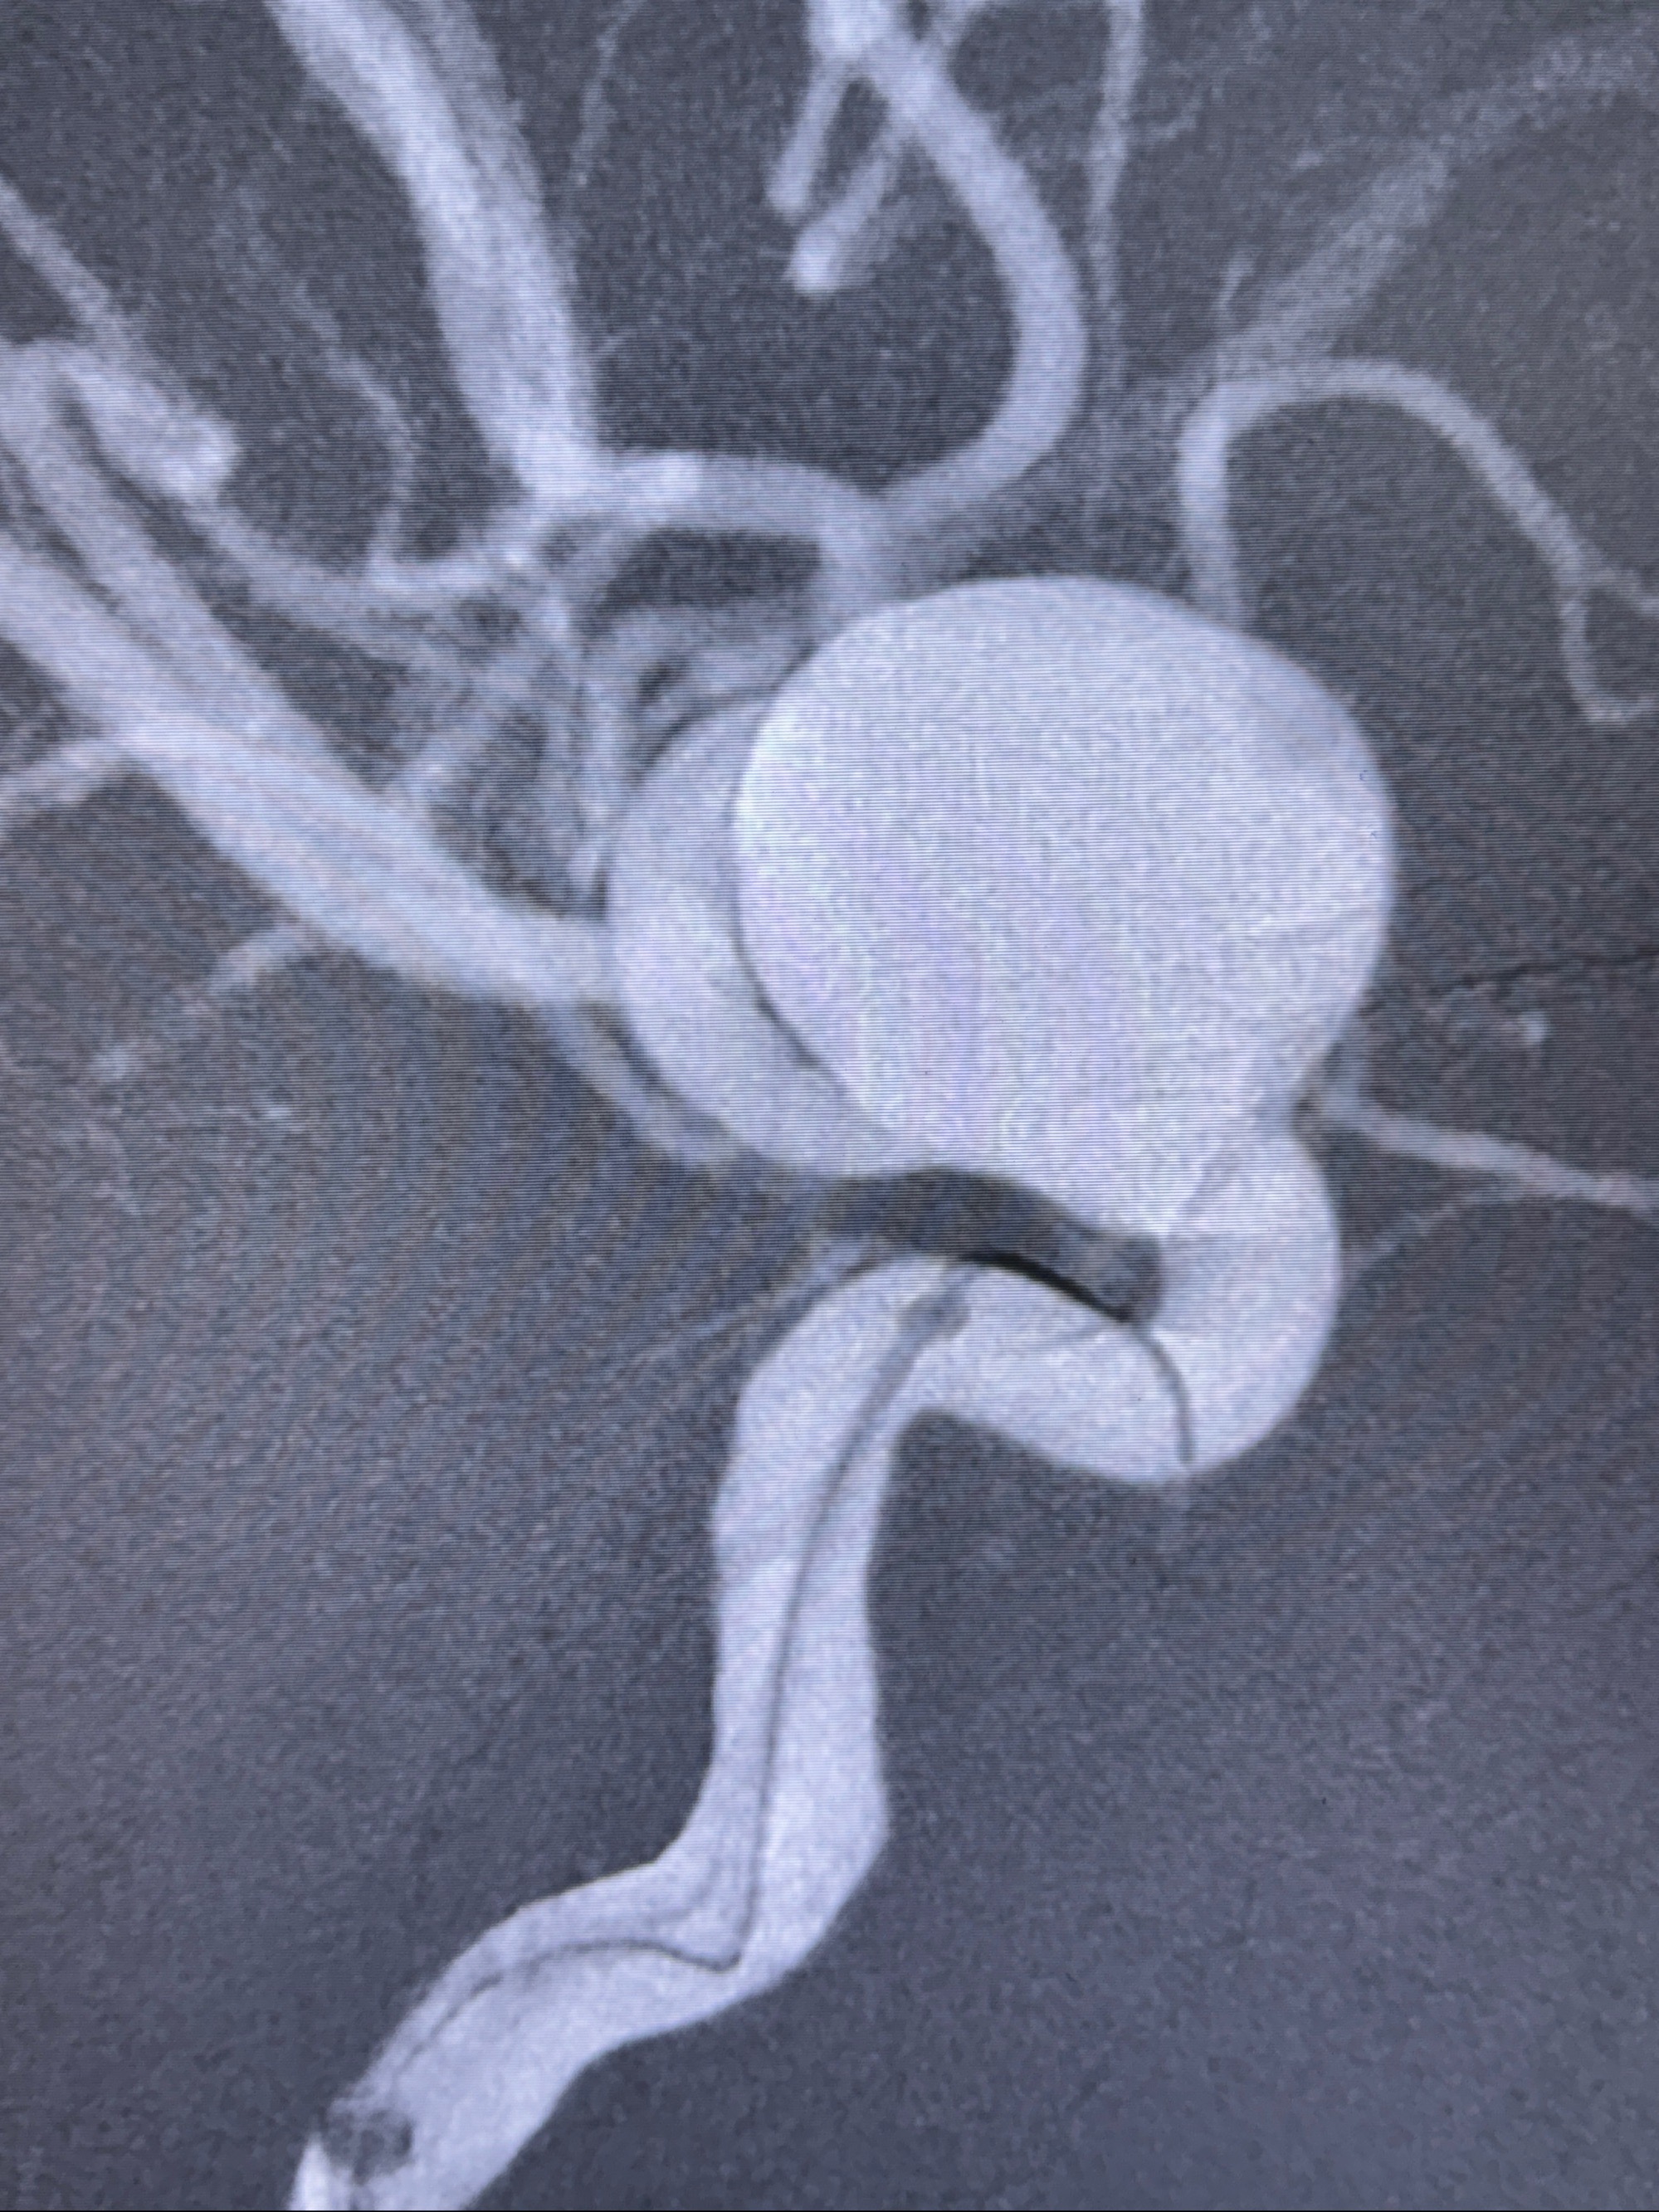

2023-12-08 复旦大学附属华山医院 全脑血管造影:右侧颈内动脉C6段动脉瘤,瘤颈6.68mm,动脉瘤大小13.28*12.34mm

2023-12-08外院DSA:右侧颈眼动脉瘤,约13*12mm大小,压颈试验显示左右向及后向前代偿可

测量动脉瘤的大小:16*13.8*7.6mm大小,较原先变大,考虑双抗后瘤内血栓溶解可能